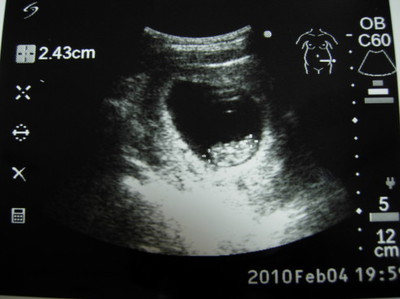

(圖/懷孕週期:9W)寶貝: 你已經2.5cm大了。馬麻每天跪趴在馬桶嘔吐不下二十次,時時刻刻都在煎熬!我也終... (詳全文)